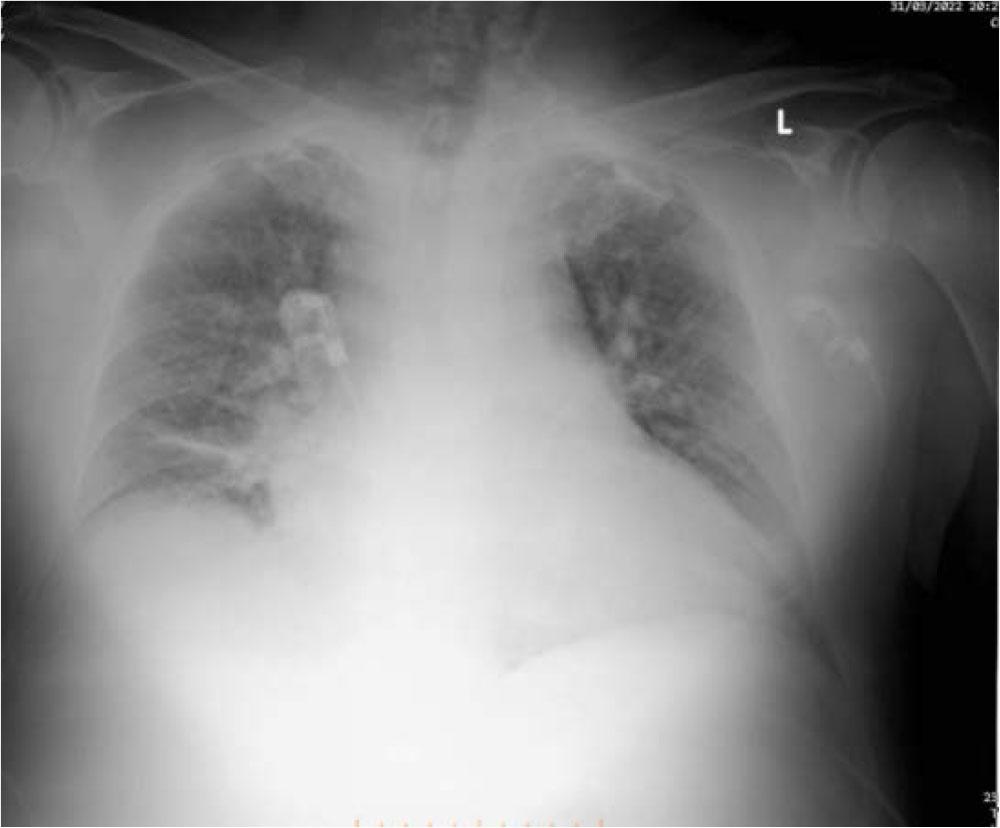

He had derangement of his lab workup, as follows: Creatinine (Cr) of 2.23 (0.55 to 1.30 mg/dL normal), blood urea nitrogen (BUN) of 100 (14 to 39 mg/dL normal), Glycemia 303 mg/dL, Troponin I 0.218 (< 1.0 ng/mL normal). His blood count (CBC) showed WBC 10.42x103qe/μl, RBC 3.75x105qel/μl, Hb 10.7 g/dL. An arterial blood gas (ABG) a pH of 7.31, hyperkalemia K+of 6.54 mEq/L (3.8–5.0 mEq/L normal), base excess (BE) of −11.1, (−2/+2 normal). The thoracic X-Ray revealed opacification of both lungs, probably pulmonary edema. Figure 1

Thoracic X Ray, bilateral opacification